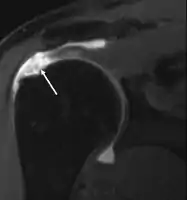

MRI

Magnetic resonance imaging (MRI) and ultrasound[41] are comparable in efficacy and helpful in diagnosis although both have a false positive rate of 15–20%.[42] MRI can reliably detect most full-thickness tears although very small pinpoint tears may be missed. In such situations, an MRI combined with an injection of contrast material, an MR-arthrogram, may help to confirm the diagnosis. It should be realized that a normal MRI cannot fully rule out a small tear (a false negative) while partial-thickness tears are not as reliably detected.[43] While MRI is sensitive in identifying tendon degeneration (tendinopathy), it may not reliably distinguish between a degenerative tendon and a partially torn tendon. Again, magnetic resonance arthrography can improve the differentiation.[43] An overall sensitivity of 91% (9% false negative rate) has been reported indicating that magnetic resonance arthrography is reliable in the detection of partial-thickness rotator cuff tears.[43] However, its routine use is not advised, since it involves entering the joint with a needle with potential risk of infection. Consequently, the test is reserved for cases in which the diagnosis remains unclear.